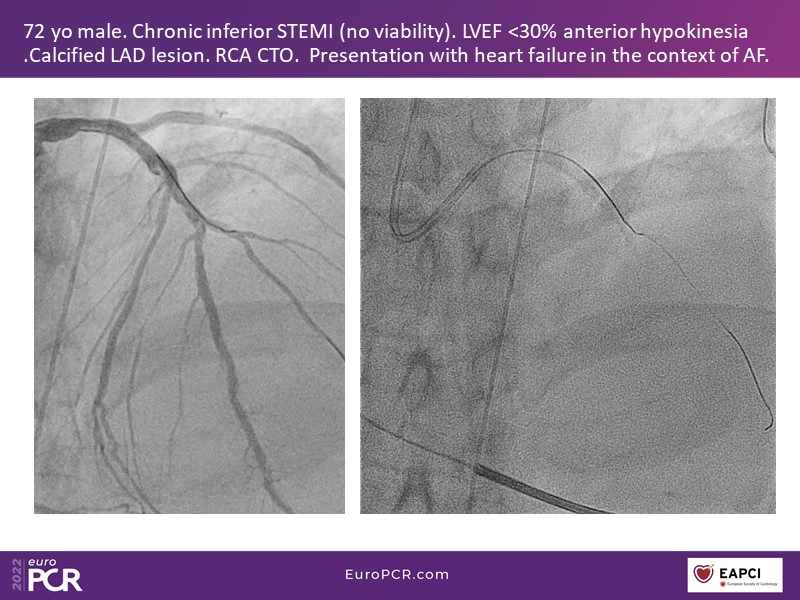

Conquer calcium with intravascular lithotripsy (IVL): cases and clinical data

This EuroPCR 2022 session mainly focuses on the DISRUPT CAD studies: hear discussion on the latest DISRUPT CAD clinical evidence supporting the use of IVL across different calcium morphologies, appraise the most recent one-year OCT-pooled analysis of the DISRUPT CAD III and IV studies, and learn about the differences in female PCI outcomes with IVL versus Rota.